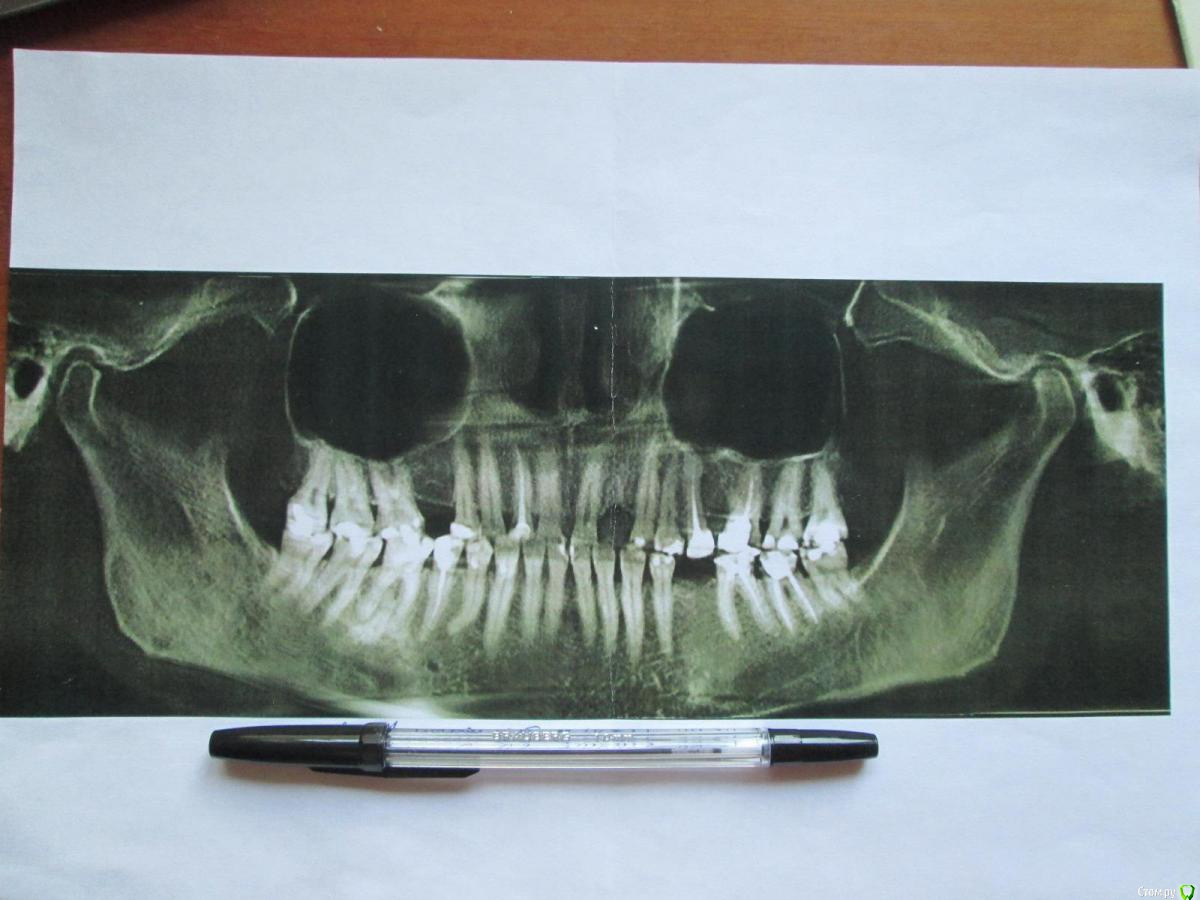

37-й зуб. Депульпирован, стояла большая пломба. В 2013 году  откололась наружная стенка зуба, скол близко к корню. Стоматологом № 1 был поставлен штифт, коронка восстановлена пломбой (фото с торчащим штифтом от 2013 года). Через год наружная часть пломбы откололась прямо по штифту, так ходила три года, ничего не царапало, не мешало. В 2016 году стоматолог № 2 в поликлинике уговорила запломбировать, в результате сделала скошенную наружную часть пломбы. Фото ротовой полости справа от 07.2019 г. прилагаю.

Вопрос: что делать с 37-й зубом? Хирург не хочет удалять, говорит, что можно восстановить пломбой, и боится повредить 36-й. Не знаю, видно ли на снимках, в каком канале стоит штифт и можно ли поставить еще один штифт (второй штифт врач не поставила, насколько я помню, из-за того, что будет дороже и еще что-то там может не выдержать). Без второго штифта пломба, повторяющая анатомическую форму зуба, я считаю, простоит максимум год. С 36-м зубом тоже непонятно что делать, не идет ли там процесс кариеса на корне…

Между корнями что-то черное (на КТ и 2016 года и 05.2019 года). Не хотелось бы покрывать коронкой зуб с гранулемой между корнями. Стоматолог предложил рассверлить пломбу и посмотреть.